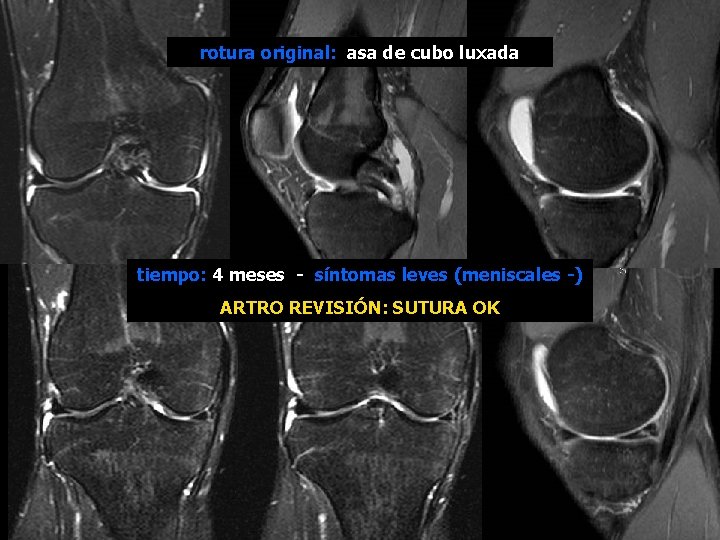

rotura original: asa de cubo luxada tiempo: 4 meses - síntomas leves (meniscales -) ARTRO REVISIÓN: SUTURA OK